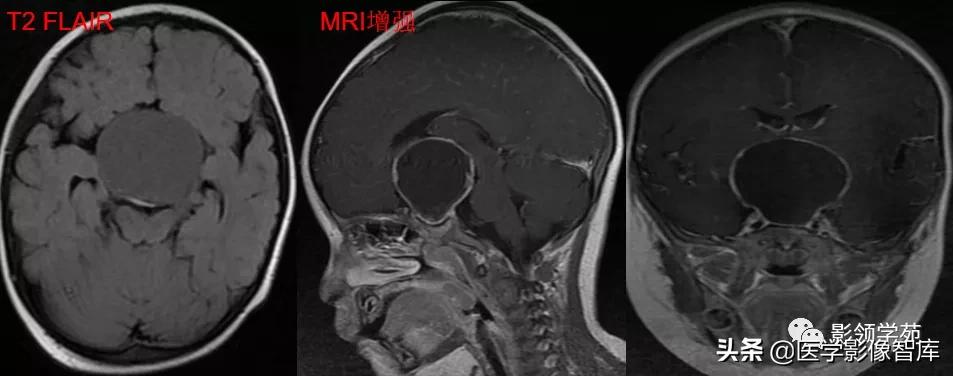

男,2岁,双视力障碍

鞍区见一类圆形囊性肿块,呈长T1长T2信号,囊壁厚薄不均。

囊壁呈环状强化,囊内未见明显强化。病灶占据蝶鞍、鞍上池及第三脑室前部,边缘清楚。

鞍区见一类圆形囊性肿块,囊壁呈蛋壳样钙化。肿块向下压入蝶鞍,向上达到第三脑室水平。